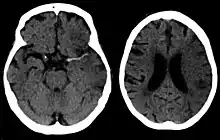

Silent stroke

A silent stroke is a stroke that does not have any outward symptoms, and people are typically unaware they have had a stroke. Despite not causing identifiable symptoms, a silent stroke still damages the brain and places the person at increased risk for both transient ischemic attack and major stroke in the future. Conversely, those who have had a major stroke are also at risk of having silent strokes.[54] In a broad study in 1998, more than 11 million people were estimated to have experienced a stroke in the United States. Approximately 770,000 of these strokes were symptomatic and 11 million were first-ever silent MRI infarcts or hemorrhages. Silent strokes typically cause lesions which are detected via the use of neuroimaging such as MRI. Silent strokes are estimated to occur at five times the rate of symptomatic strokes.[55][56] The risk of silent strokes increases with age, but they may also affect younger adults and children, especially those with acute anemia.[55][57]